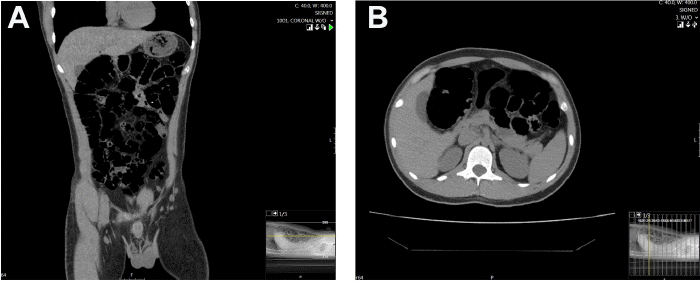

Figure 2. Lack of Foreign Object Visualization on Initial CT. Published with Permission

CT imaging without contrast was conducted shortly following patient presentation and revealed a slightly distended stomach, normal bowel caliber, and moderate gas and stool. The foreign body was not visualized on A) axial or B) coronal imaging and no evidence of free air or fluid was noted

Esophagogastroduodenoscopy was performed, and while a small abrasion on the tongue was noted, the esophagus appeared normal, and the foreign object was not successfully visualized. CT imaging without contrast from the lung bases through the pelvis revealed a slightly distended stomach, normal bowel caliber with scattered fluid in the small bowel, as well as a normal appendix, and moderate stool and gas through the colon with no free air, fluid, or evidence of a visible foreign body (Figure 2).